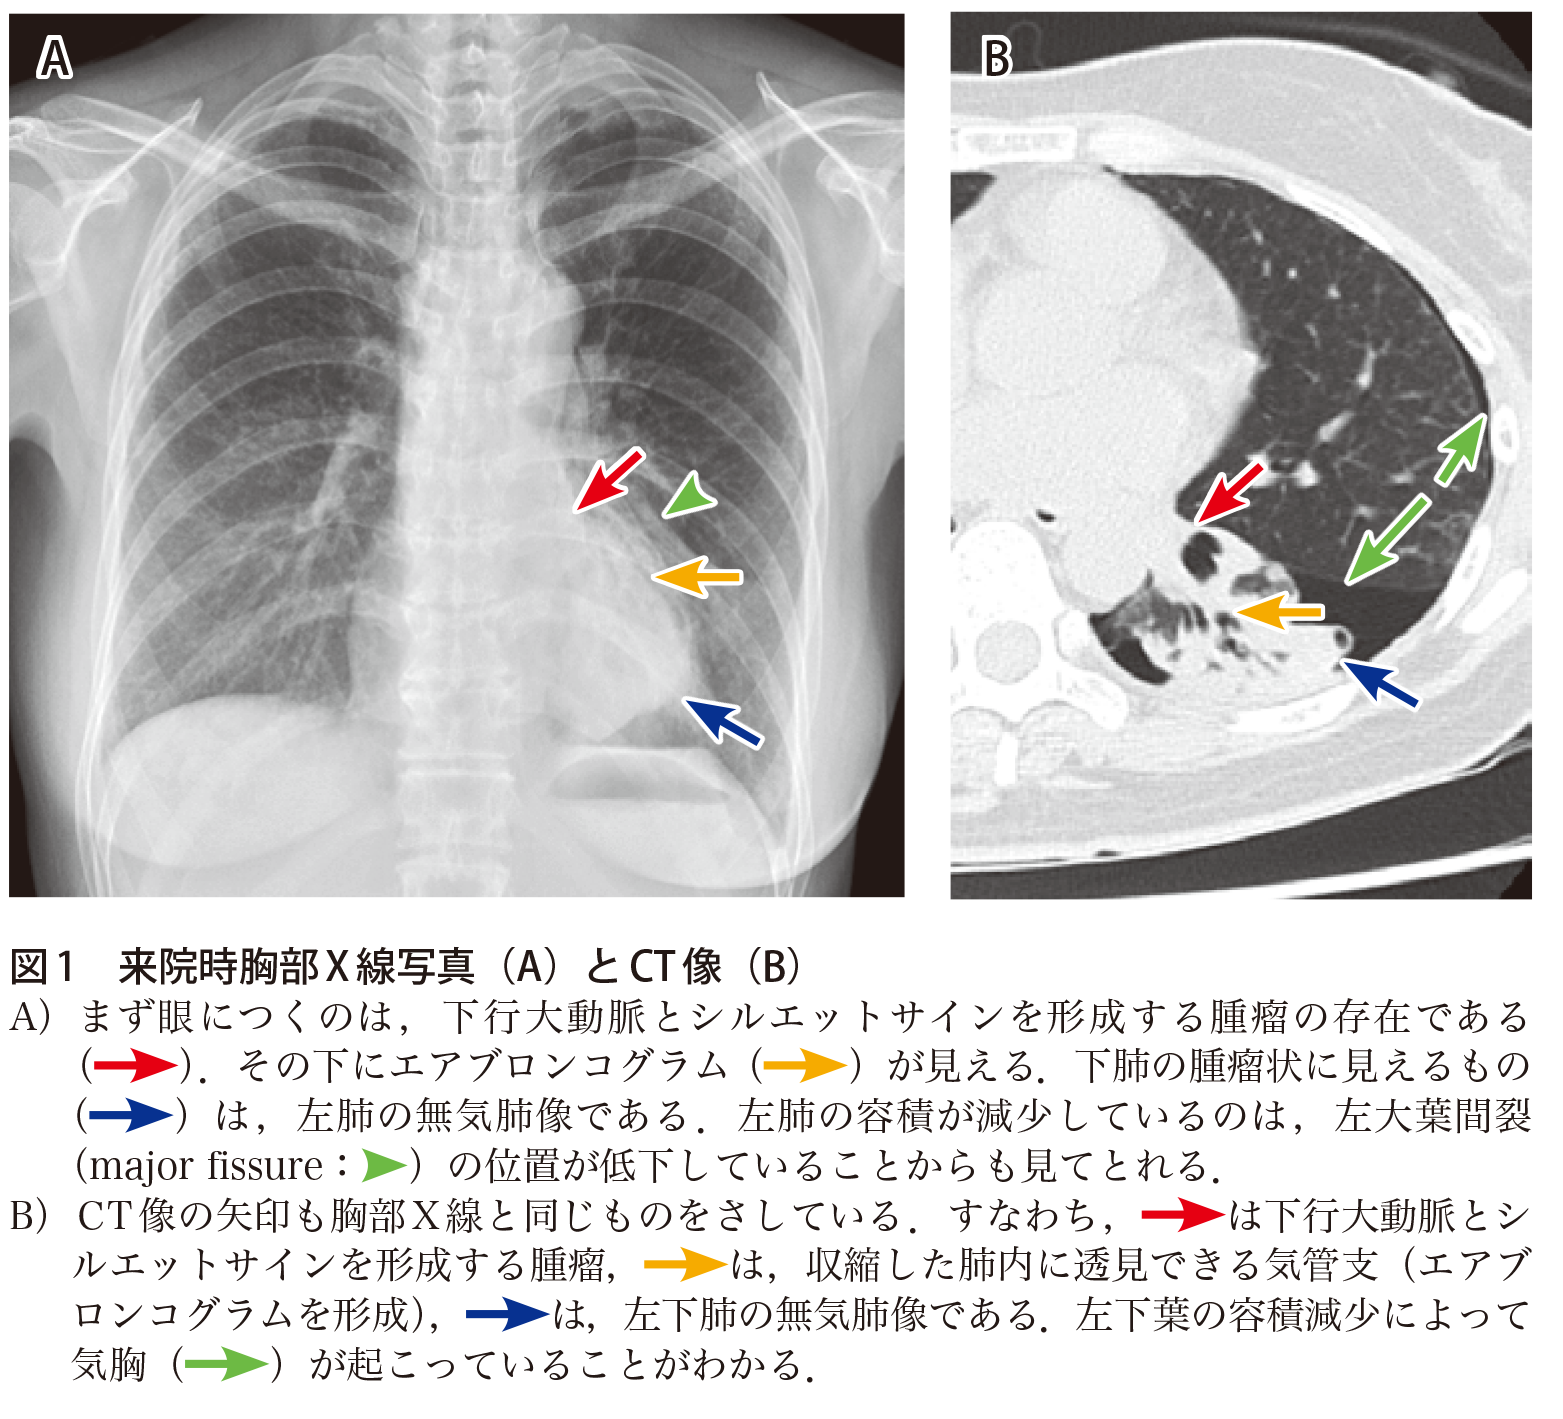

円形無気肺の画像所見 円形あるいは類円形の腫瘤影 を形成する。 胸膜肥厚 を伴うことが多い。 胸水 の既往があることが多い。 無気肺部に向かって近くの気管支と動脈が、弯曲する comettail sign(彗星の尾に似ている) を認めることあり。 症例 80歳代男性キー画像54 気管支内に鋳型状に充満する腫瘍と末梢肺の変化 末梢側:粘液栓、エアートラッピング、無気肺 ※白黒反転画像では、fingeringlove sign、treeinbud signの検出が容易で、またエアートラッピングのコントラストも良好。左下葉無気肺が生じている(左下肺野心 陰影に重なる部分の透過性低下,下行大動脈左側縁および左横隔 膜影は不明瞭化し,左肺全体の容積減少)。 c.左下葉支基部の扁平上皮癌により左下葉は完全無気肺に陥って いるのがct画像により確認できる。